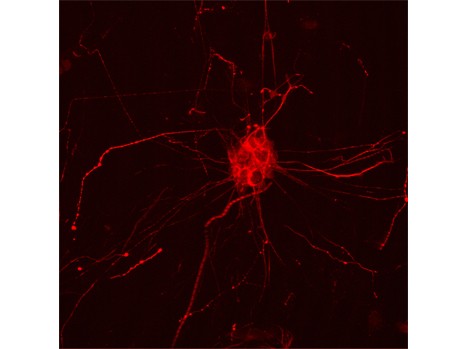

Marcatura fluorescente della proteina Tau in una cellula umana (Fonte: HNT © Inserm / U837)Sappiamo da alcuni anni che l'Alzheimer è caratterizzato da due tipi di lesioni: le placche amiloidi e la proteina tau degenerata.